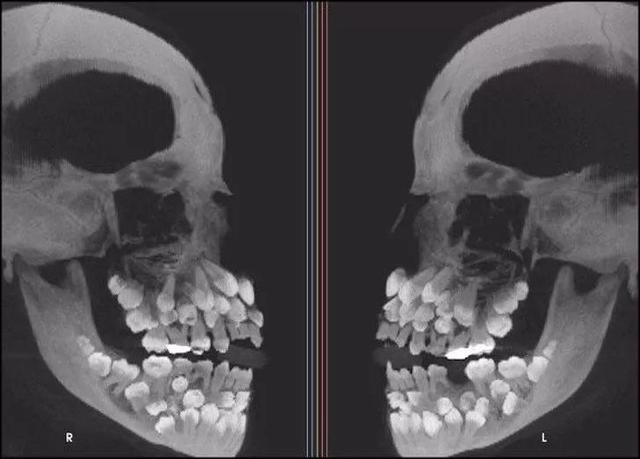

“多齿症”患者的X光照片